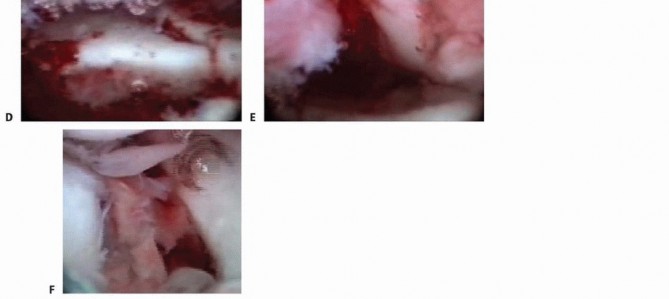

### TECH FIG 2 • A. PA view showing an impacted scaphoid facet fracture fragment with an obvious injury to the SLIL. B. Lateral view showing a dorsal rim fracture fragment. C. The arthroscope is in the 6R portal, demonstrating the impacted scaphoid facet fracture fragment. This would be quite difficult to view through an open arthrotomy but is well visualized arthroscopically under bright light and magnified conditions. D. The impacted scaphoid facet fragment is elevated back to the volar rim, using the rim as a landmark to judge rotation. E,F. Geissler grade III tear involving the SLIL as seen through the 3-4 portal (E) and the radial midcarpal portal (F).(continued) Suspend the wrist in the traction tower, establish portals, and evacuate the fracture debris and hematoma. The depressed lunate facet fragment is best seen with the arthroscope in the 3-4 portal ( TECH FIG 2C,D). Percutaneously place an 18-gauge needle directly over the depressed fragment as viewed arthroscopically. Insert a large K-wire about 2 cm proximal to the previously placed 18-gauge needle to percutaneously elevate the depressed lunate facet fragment.

TECH FIG 2 • (continued) G,H. PA and lateral radiographs showing anatomic reduction to the impacted scaphoid facet fracture. (The tear of the SLIL also was acutely repaired.) Use a bone tenaculum to further diminish the gap between the radial styloid and lunate facet fragments. Place guidewires transversely under the subchondral surface of the radius from the radial styloid into the anatomically reduced lunate facet fragment. It is important to pronate and supinate the wrist following placement of the transverse pins to ensure the guidewires have not violated the DRUJ. The concave nature of the DRUJ makes radiographic assessment difficult. Consider insertion of bone graft to support the reduced lunate fragment and avoid late settling. Make a small incision between the fourth and fifth dorsal compartments. Use cancellous allograft bone chips or bone substitutes. If feasible, place headless cannulated screws to stabilize both the radial styloid and the impacted lunate facet fragments ( TECH FIG 2E-H). 2. ## Three-and Four-Part Fractures with Metaphyseal Comminution A combination of open surgery, using a volar plate for stability, and arthroscopy, as an adjunct to assist the articular reduction, is used if metaphyseal comminution is present ( TECH FIG 3). Volar plate stabilization is very stable and allows for early range of motion and rehabilitation as compared to K-wires or headless screws alone.

### TECH FIG 4 • A. A standard volar approach is made, centered over the flexor carpi radialis tendon, and the fracture site is exposed. B. A volar distal radius locking plate is applied. The initial screw is placed through the proximal plate to secure the plate to the shaft. C. The intra-articular reduction is viewed under fluoroscopy and provisionally pinned. A displaced intra-articular fracture fragment can still be identified. D. The arthroscope is in the 3-4 portal, showing the volar capsule blocking reduction of the radial styloid fragment. E. Joysticks previously inserted into the radial styloid fragment are then used to control and anatomically reduce the radial styloid fragment. F. The arthroscope is in the 6R portal looking across the wrist. Anatomic reduction of the radial styloid fragment is documented. G. Once the anatomic restoration of the articular surface is evaluated both arthroscopically and fluoroscopically, the distal screws are placed in the plate. H. Fluoroscopic view showing anatomic restoration to the articular surface of the distal radius. I. The patient had an associated osteochondral fracture of the lunate, not visible on plain radiographs. The displaced fragment is arthroscopically removed.

Apply a volar distal radius locking plate to stabilize the volar bone fragments ( TECH FIG 4B). Place a screw in the proximal portion of the plate first to reduce the plate to the shaft. Provisionally pin the distal fragments through the plate. Manipulate the articular fragments under fluoroscopy to obtain as anatomic a reduction as possible ( TECH FIG 4C,D). Suspend the wrist in the traction tower and reduce the articular fragments arthroscopically ( TECH FIG 4E,F). If articular reduction is not anatomic, remove the pins and fine-tune the reduction. Once the fracture reduction is thought to be anatomic, place the distal screws through the plate ( TECH FIG 4G-I). It is important that the fracture be reduced to the plate, with no gap between the plate and the bone. This can be achieved by flexion of the wrist in the tower and by insertion of a nonlocking screw first, before the insertion of standard locking screws. Place the remaining proximal and distal screws if the reduction is anatomic under both fluoroscopy and arthroscopy. 1. ### Reduction and Stabilization of a Dorsal Die-Punch Fragment It is not possible to see the reduction of a dorsal die-punch fragment through the volar approach when stabilized with a plate. Arthroscopy can be helpful in this scenario. Insert the volar plate as previously described and provisionally fix the device to the radius. Frequently, the dorsal fragment may still be slightly proximal in relation to the radial shaft. The dorsal die-punch fragment is best seen with the arthroscope in the 6R portal. Establish the volar radial portal between the radioscaphocapitate ligament and the long radiolunate ligament, as viewed directly through the previous performed volar approach. 23 Percutaneously elevate and anatomically reduce the dorsal diepunch fragment as viewed arthroscopically. Once this has been achieved, place the screws into the plate and observe their path arthroscopically to ensure adequate stabilization of the dorsal die-punch fragment. 2. ## Ulnar Styloid Fractures Following anatomic reduction of the distal radius fracture, insert the arthroscope in the dorsal 3-4 portal and the probe in the 6R portal. Palpate the tension of the articular disc. Good tension indicates that the majority of the peripheral TFCC fibers are intact or still attached to the proximal ulna. A peripheral tear of the articular disc is repaired arthroscopically when detected. 30 Stabilization of a large ulnar styloid fragment is considered when the articular disc is lax by palpation and no peripheral TFCC tear is identified ( TECH FIG 5). In this instance, the majority of the fibers of the TFCC are attached to the displaced ulnar styloid fragment. Make a small incision between the extensor carpi ulnaris and the flexor carpi ulnaris tendons and identify the fracture site. Retrieve the distal fragment, which often displaces in a distal and radial direction. Mobilize the styloid fragment using a no. 15 blade, taking care to protect the TFCC insertion. Reduce the fragment anatomically, under direct visualization, and insert a guidewire in a retrograde manner for provisional stability. Stabilize the ulnar styloid fragment using either a tension band technique (with wire and two K-wires) or, preferably, using a micro headless cannulated screw. Place the cannulated headless screw over the guidewire and verify fracture reduction with fluoroscopy. Insert the arthroscope into the 3-4 portal and the probe into the 6R portal to document restoration of TFCC tension.